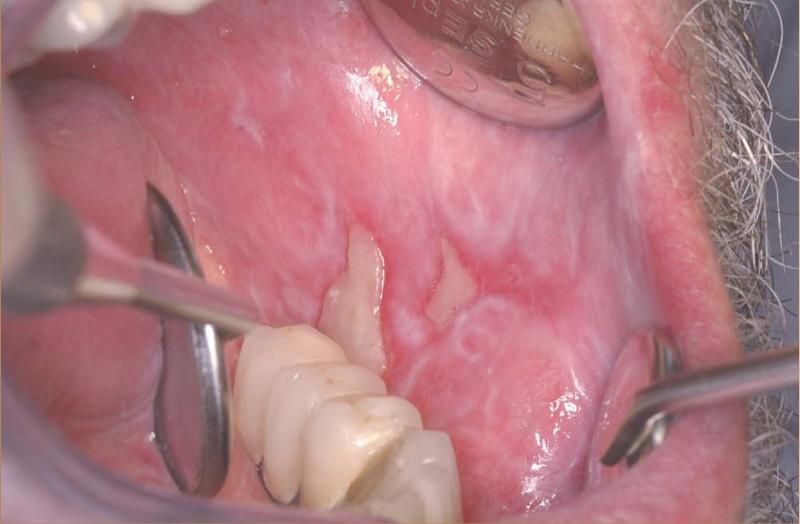

Descripción del caso Un varón de 57 años refiere que hace seis meses empezó a sentir molestias en el lado derecho de la lengua, que han ido en aumento y actualmente le...